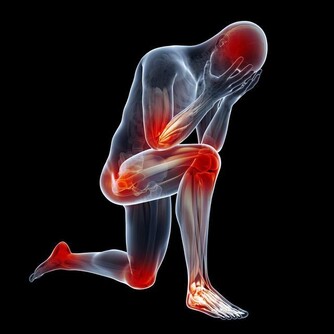

2.頸椎發硬

腦梗爆發之前,肢體會出現不聽使喚的感覺,通常表現為頸椎發硬,低頭的時候,下頜難以抵到上胸。如果排除由於長時間久坐導致,應當及時就醫,不可忽視。